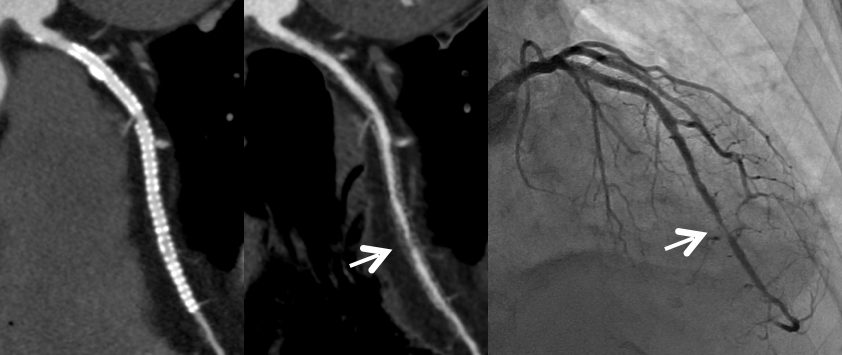

サブトラクション冠動脈CT

これまで、CTでは評価が難しいとされている冠動脈の強い石灰化部位やステント治療部位において、我々が考案した特殊な撮影(test bolus tracking法)および画像処理技術を用いて評価可能な画像を可能な限り提供しています。

Yamaguchi T. Ichikawa K, Takahashi D. et.al. A New Contrast Enhancement Protocol for Subtraction Coronary Computed Tomography Requiring a Short Breath-Holding Time. Academic Radiology Published online: October 17, 2016